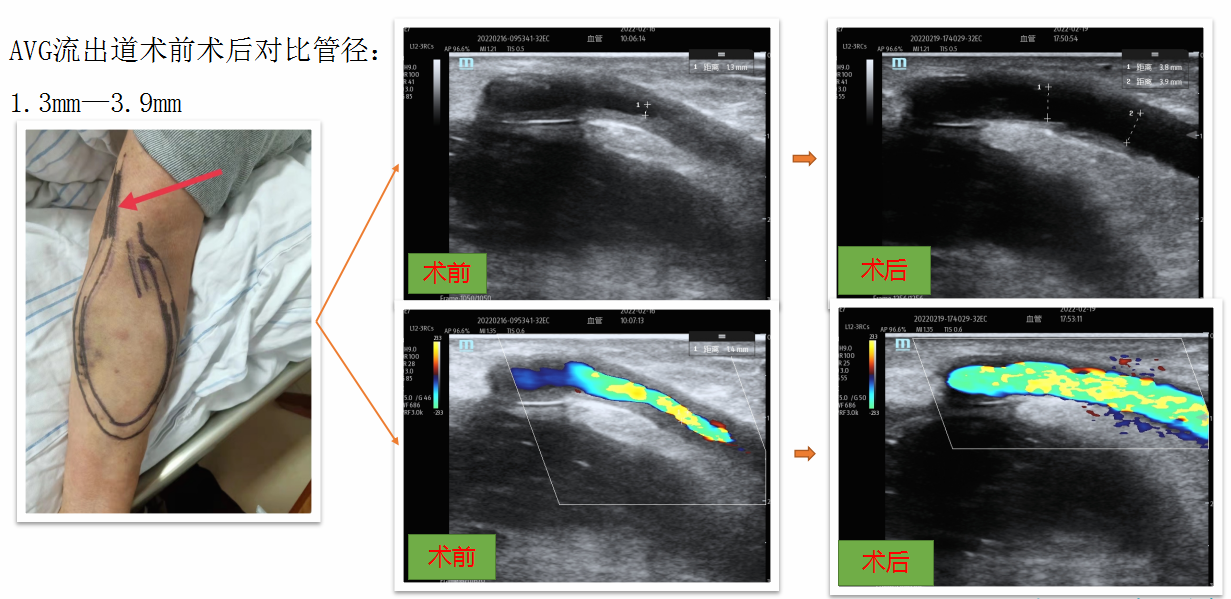

血管通路全周期“手术与介入”技术:

通路建立维护技术成熟,常规开展自体动静脉内瘘成形术、人工血管动静脉造瘘术、动脉瘤修补、深静脉临时及长期导管置管术等。

高位内瘘(穿静脉内瘘)

人工血管动静脉造瘘术

疑难复杂并发症介入处理能力强:

常规开展超声介入及DSA(数字减影血管造影)引导下的动静脉内瘘球囊扩张术、中心静脉狭窄扩张术、外周血管支架置入术及疑难长期导管置换,实现血管通路的“建立-维护-并发症处理”全周期诊疗管理。